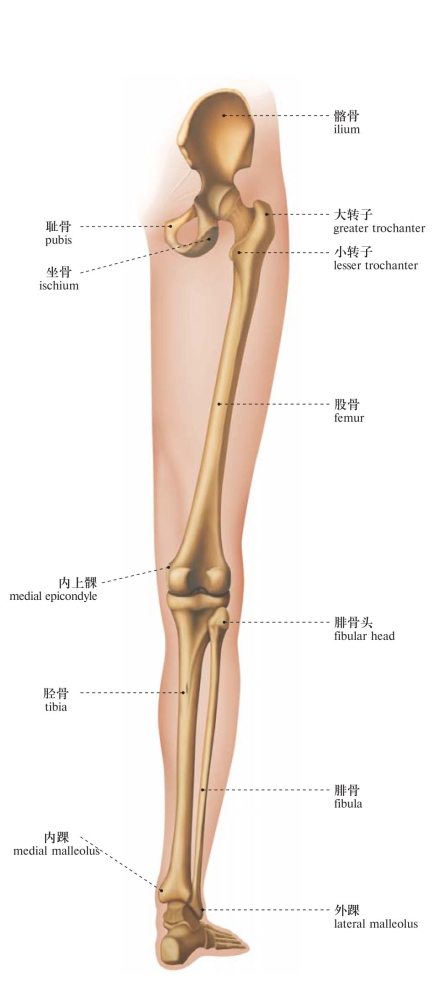

图101 下肢骨(后面观)

Bones of the lower limb (posterior aspect)